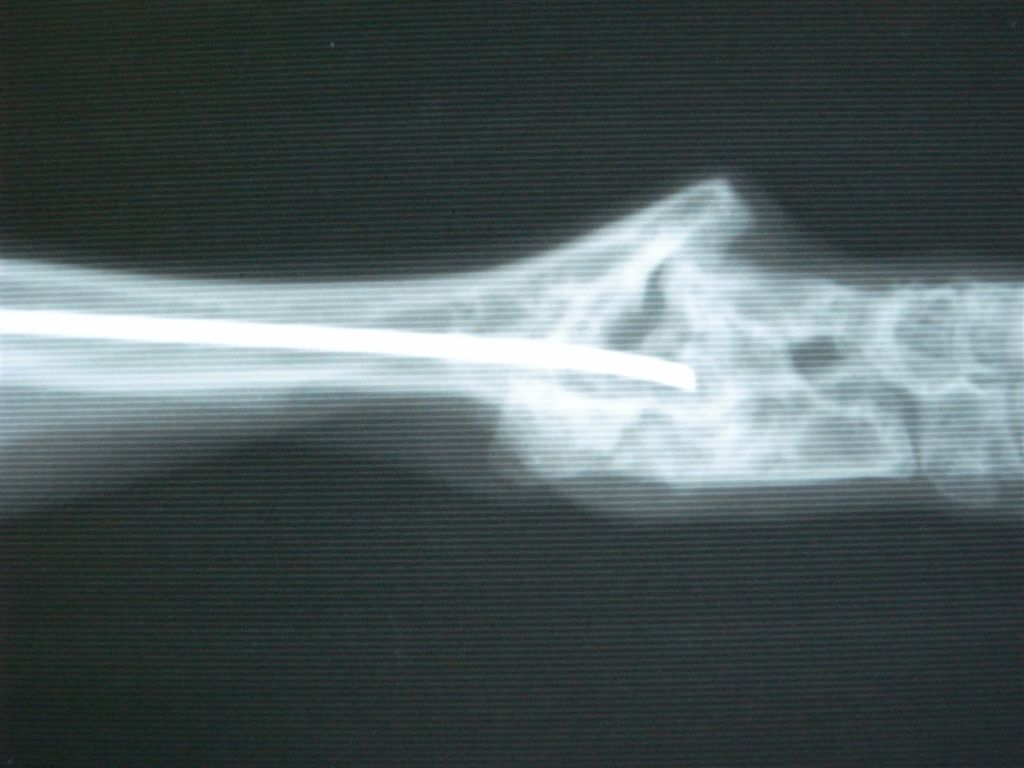

うさぎ、踵の骨折、骨髄内にピンをいれて固定。

関節に近い骨折だと固定が関節ごと固定するので稼動域が狭くなりやすい。